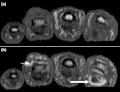

T1-weighted semi-coronal MRI of sacroiliac joints (a) before and (b) after contrast showing active sacroiliitis (arrow). -

(a) STIR Sagittal MRI of ankle showing enthesitis at Achilles tendon insertion (thick arrow), synovitis of ankle joint (long thin arrow), and bone marrow edema at tendon insertion (short thin arrow). T1-weighted images, before (b) and after (c) contrast, show enthesitis (large arrow) and bone erosion at tendon insertion (short thin arrows).